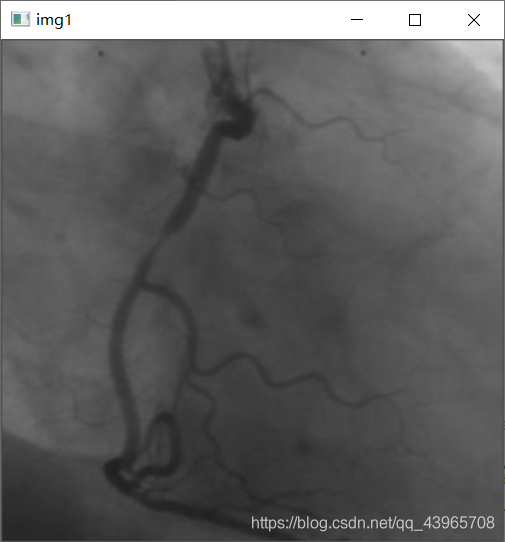

# 显示灰度图

img = cv2.imread(r"C:UserspcDesktopvas0.png",0)

cv2.imshow("img1",img)

运行结果